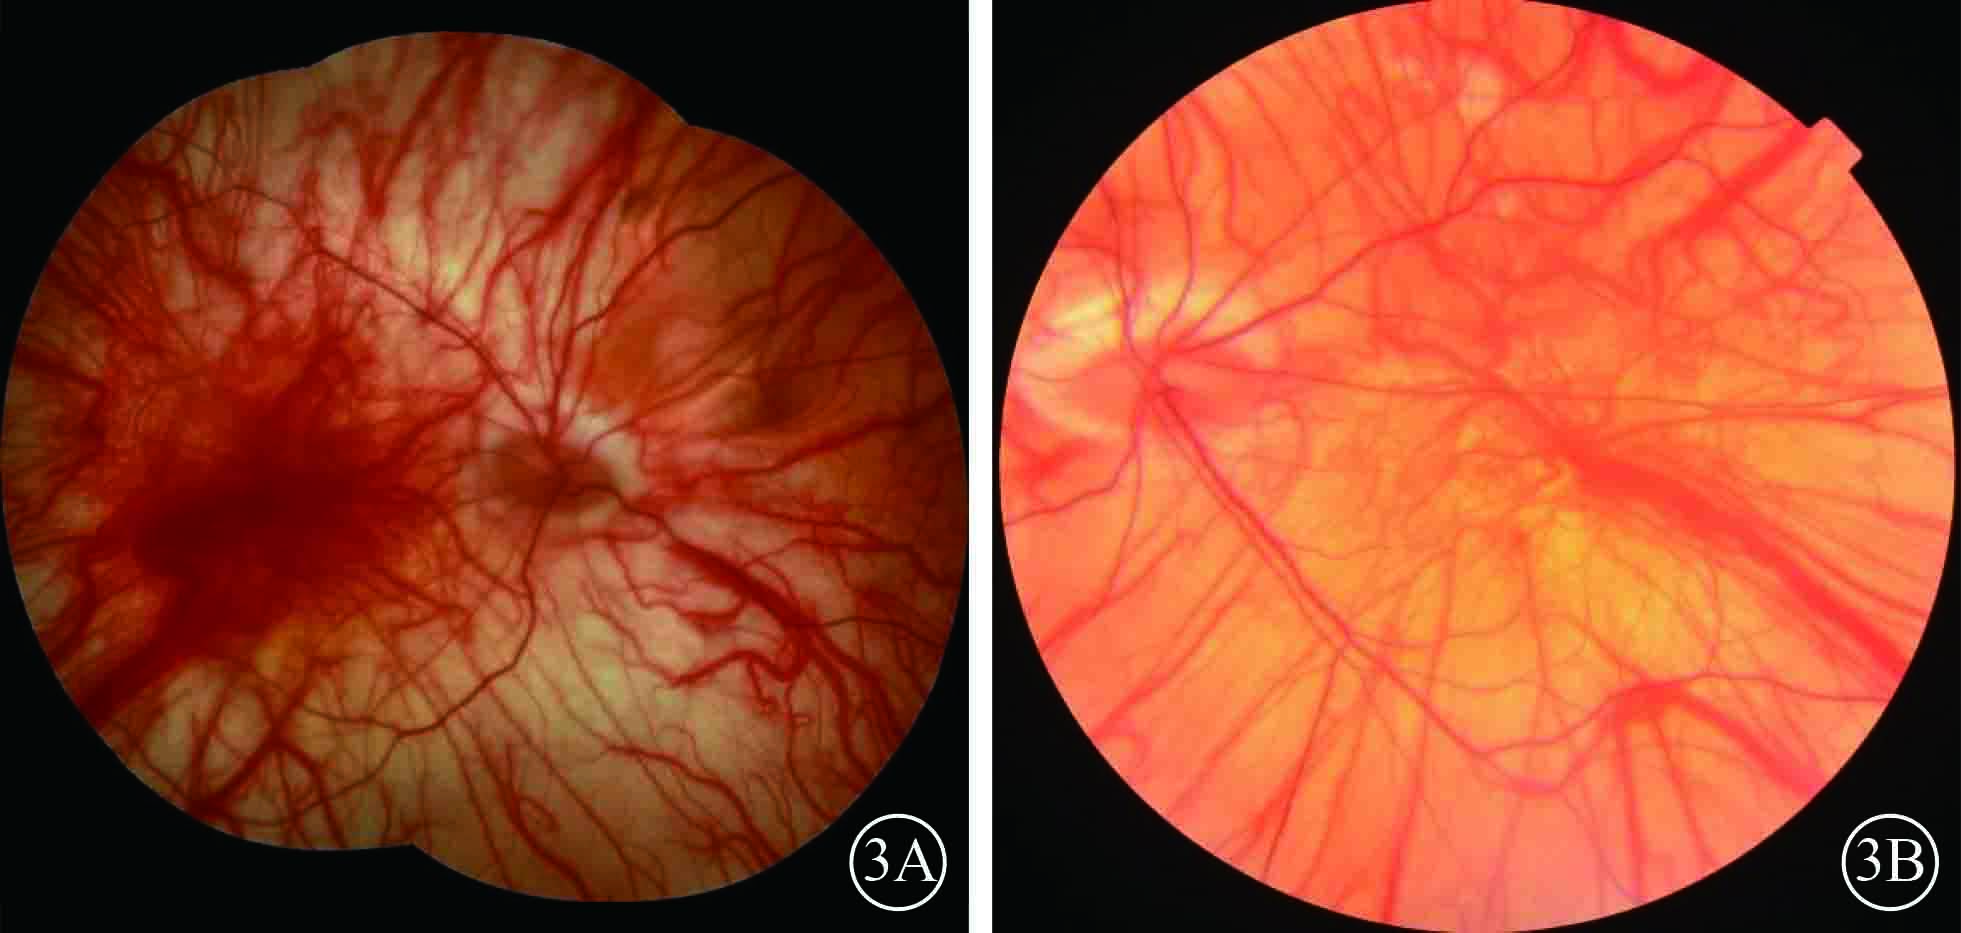

患者男,35歲。因體檢發現雙眼視網膜脫離1月余于2015年3月12日來我院眼科就診。患者自幼皮膚、毛發、虹膜無色素;雙眼視力差、畏光。否認外傷史、家族史。眼部檢查:右眼視力數指/30 cm,左眼視力0.1;雙眼矯正視力均無提高。雙眼眼瞼皮膚及睫毛均無色素;眼球水平震顫;角膜透明,瞳孔圓,虹膜半透明;晶狀體透明。雙眼眼底呈橙色。右眼全視網膜脫離,左眼0~8點時鐘位視網膜脫離(圖1);雙眼視網膜裂孔均窺不清。A型超聲檢查,右眼、左眼眼軸長度分別為26、28 mm。診斷:(1)雙眼孔源性視網膜脫離(疑似);(2)雙眼高度近視;(3)眼皮膚白化病。分別于2015年3月23日、5月11日行左眼、右眼視網膜復位手術。采用標準25G經睫狀體平坦部玻璃體切割手術。手術中見左眼視網膜裂孔分別位于 1、2、4、6點時鐘位,右眼裂孔位于8、11點時鐘位。先采用眼內電凝對裂孔邊緣進行標記,電凝處理后裂孔邊緣呈白色外觀(圖2);視網膜復位后,采用視網膜冷凍替代常規激光光凝對裂孔進行封閉;最后進行硅油眼內填充。雙眼均于手術后3個月行硅油取出手術。硅油取出后3個月,雙眼視網膜復位良好,眼底呈橙色,透見脈絡膜大血管(圖3);6個月,右眼視網膜復位良好,左眼下方視網膜再次脫離。于2016年2月1日再次行左眼視網膜復位手術、硅油填充。2016年12月27日隨訪,右眼視網膜復位良好;左眼硅油填充,下方視網膜仍有局部脫離(圖4)。

硅油取出手術后3個月雙眼彩色眼底像。3A. 右眼;3B.左眼。雙眼視網膜復位,眼底無色素,透見脈絡膜大血管

硅油取出手術后3個月雙眼彩色眼底像。3A. 右眼;3B.左眼。雙眼視網膜復位,眼底無色素,透見脈絡膜大血管

患者男,35歲。因體檢發現雙眼視網膜脫離1月余于2015年3月12日來我院眼科就診。患者自幼皮膚、毛發、虹膜無色素;雙眼視力差、畏光。否認外傷史、家族史。眼部檢查:右眼視力數指/30 cm,左眼視力0.1;雙眼矯正視力均無提高。雙眼眼瞼皮膚及睫毛均無色素;眼球水平震顫;角膜透明,瞳孔圓,虹膜半透明;晶狀體透明。雙眼眼底呈橙色。右眼全視網膜脫離,左眼0~8點時鐘位視網膜脫離(圖1);雙眼視網膜裂孔均窺不清。A型超聲檢查,右眼、左眼眼軸長度分別為26、28 mm。診斷:(1)雙眼孔源性視網膜脫離(疑似);(2)雙眼高度近視;(3)眼皮膚白化病。分別于2015年3月23日、5月11日行左眼、右眼視網膜復位手術。采用標準25G經睫狀體平坦部玻璃體切割手術。手術中見左眼視網膜裂孔分別位于 1、2、4、6點時鐘位,右眼裂孔位于8、11點時鐘位。先采用眼內電凝對裂孔邊緣進行標記,電凝處理后裂孔邊緣呈白色外觀(圖2);視網膜復位后,采用視網膜冷凍替代常規激光光凝對裂孔進行封閉;最后進行硅油眼內填充。雙眼均于手術后3個月行硅油取出手術。硅油取出后3個月,雙眼視網膜復位良好,眼底呈橙色,透見脈絡膜大血管(圖3);6個月,右眼視網膜復位良好,左眼下方視網膜再次脫離。于2016年2月1日再次行左眼視網膜復位手術、硅油填充。2016年12月27日隨訪,右眼視網膜復位良好;左眼硅油填充,下方視網膜仍有局部脫離(圖4)。

硅油取出手術后3個月雙眼彩色眼底像。3A. 右眼;3B.左眼。雙眼視網膜復位,眼底無色素,透見脈絡膜大血管

硅油取出手術后3個月雙眼彩色眼底像。3A. 右眼;3B.左眼。雙眼視網膜復位,眼底無色素,透見脈絡膜大血管